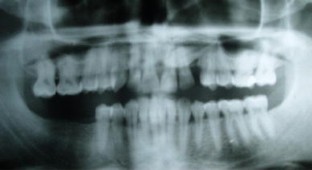

Fig. 1